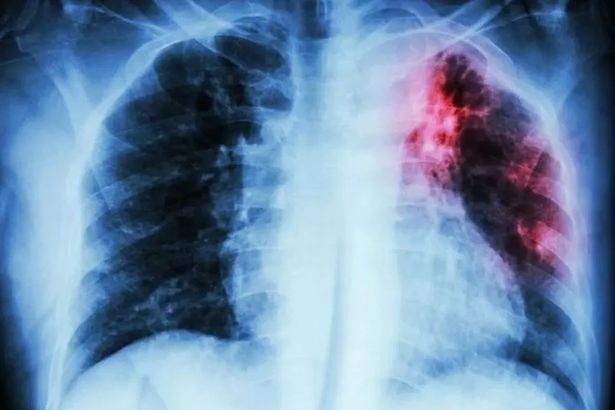

The Victorian superbug that’s on the rise in Lancashire as hotspots named

The vicious illness is often linked to areas with high levels of deprivation The vicious illness is often linked to areas with high levels of deprivation Lancs Live – NewsRead More